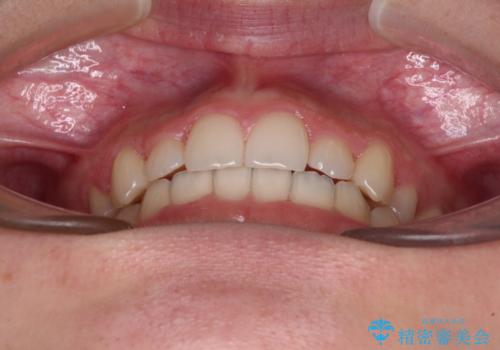

目立つ八重歯を目立たない装置で ハーフリンガルによる抜歯矯正

治療期間の目安は2年半~3年間でしたが、予定通り治療が進み、2年半弱で終えることができました。

歯列はきれいに整い、治療期間も予定通りであり、患者様には大変満足していただきました。